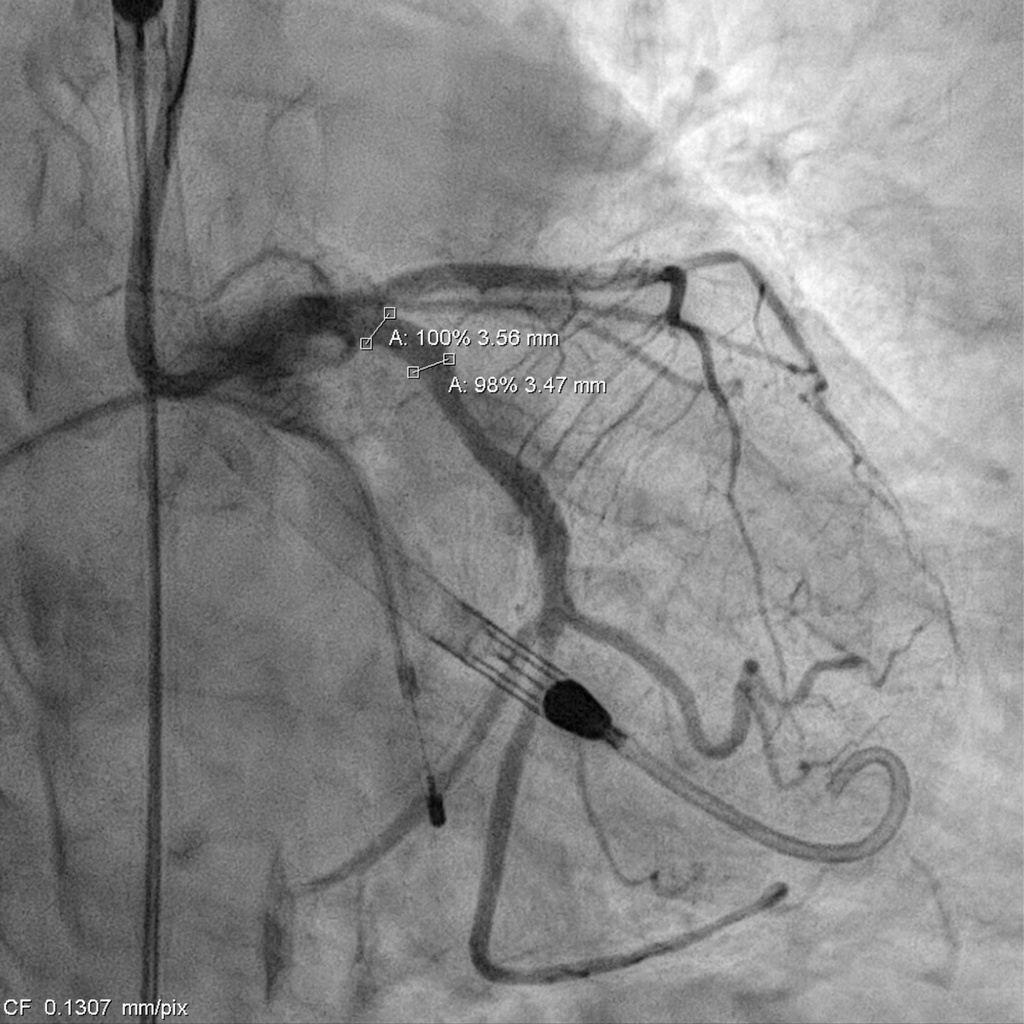

Catheterization revealed a 95% distal left main stenosis with a calcified nodule protruding into the LAD and LCX ostia, a 99% proximal LAD lesion with an additional 90% stenosis after the first diagonal branch, non-critical LCX disease, and a 70% proximal RCA lesion with multiple critical PDA stenoses. The patient and family declined PCI in the cath lab, with a Syntax score of 40.

Impella support was established before the procedure. The LCA was engaged with an EBU 3.0 ¡¿ 7 Fr guide, and a SUOH-03 wire was advanced into the LCX. A 2.0 ¡¿ 20 mm balloon was inflated across the very tight LM–LCX lesion, but IVUS still could not cross, so rotablation was performed first. The SUOH-03 wire was exchanged for a Rota Floppy using a Caravel microcatheter, and a 2.0 mm burr successfully ablated the heavily calcified, angulated LM–LCX segment.After calcium modification, a Fielder FC wire was advanced into the LAD using a reverse-wire technique. Severe mid-LAD calcification required switching to a Rota Floppy wire, and a 1.25 mm burr was used for LAD rotablation. Bradycardia occurred during Rota, so a temporary pacemaker was inserted. A 2.25 ¡¿ 15 mm NC balloon was then inflated to 12 atm to further prepare the LAD.The LAD was stented with an Onyx 2.25 ¡¿ 22 mm DES (6–16 atm) and subsequently crushed with a 3.5 ¡¿ 12 mm NC balloon. LM–LCX was stented with an Onyx 3.5 ¡¿ 15 mm DES (11–12 atm). LAD was rewired with a Sion Blue supported by a Crusade dual-lumen catheter, and stent struts were opened using 1.5 ¡¿ 10 mm and 2.5 ¡¿ 15 mm balloons. LAD-P was post-dilated with a 2.5 ¡¿ 15 mm NC (10 atm), and LM–LAD with a 2.5 ¡¿ 15 mm NC (12–18 atm). Final kissing inflation with a 3.5 ¡¿ 12 mm NC and 2.5 ¡¿ 15 mm NC balloons achieved optimal flow.The Impella was removed under stable hemodynamics, and the access site was closed with two Perclose devices without bleeding.